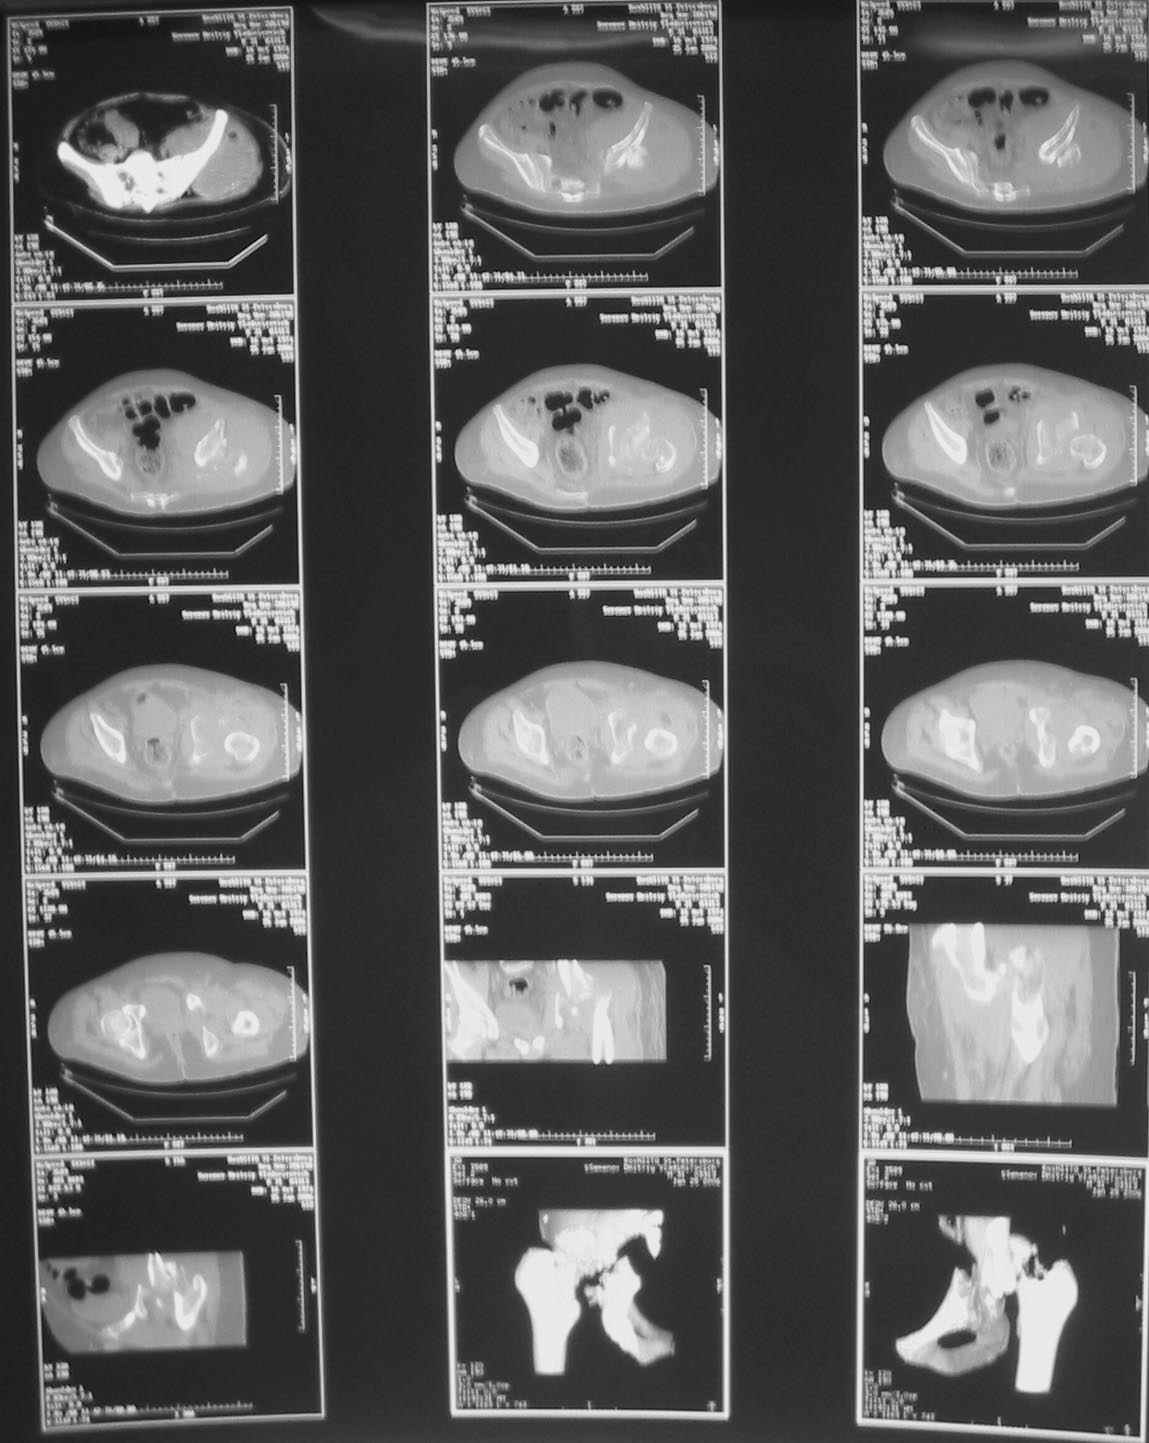

Дорогие коллеги, Поступил пациент, 5 месяцев, как сломался.

Поступил для эндопротезирования, но наши корифеи засомневались, не собрать ли сначала таз. Есть ли смысл собирать аппаратом закрыто?

Вариант с постепенной репозицией возможен, у нас такие операции были - аппаратом с введением стержней через вертельную зону в лонно-седалищный фрагмент с подтягиванием его латерально и дистально до максимального контакта задней колонны, затем открытый остеосинтез впадины с заполнением дефекта всем, чем попало. Через 2-3 мес. - эндопротез стандартным доступом, делали винтовую чашку.

Однако, учитывая вывих, 5-месячный срок мы бы, наверно, без аппарата сразу забрались в сустав с целью его реконструкции и остеосинтеза винтами и пластинами. Если удастся сделать остеосинтез хорошо - сразу сделать и эндопротез. Доступ - есссно, не как на протез, а как на впадину - или Y-образный с остеотомией болшого вертела, или латеральный. В случае подозрения на нестабильность впадины после остеосинтеза или больших трудностей при синтезе - засунуть головку во впадину, сделать остеосинтез шейки винтами, и дождаться сращения впадины, попытавшись сохранить движения в суставе. Пишут, можно противопротрузионными кольцами или Octopus укрепить остеосинтез впадины, и тогда тоже делать протез сразу, но у нас такого опыта нет, в основном предпочитали делать в два этапа - сначала реконструкция впадины, потом протез, потому что в застарелых случаях впадина сильно кривая.